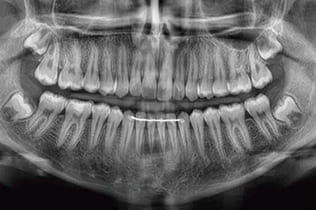

CT・レントゲン撮影

レントゲン検査

CT検査